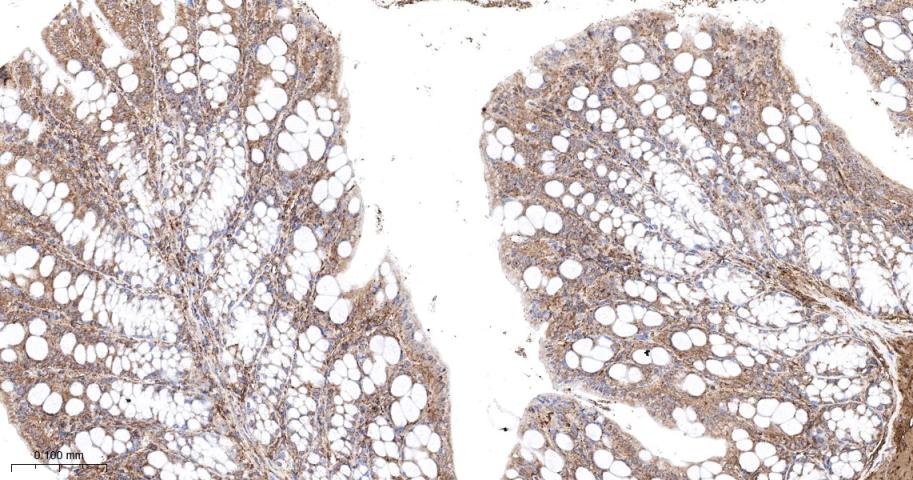

Paraformaldehyde-fixed, paraffin embedded Rat Colon; Antigen retrieval by boiling in sodium citrate buffer (pH6.0) for 15 min; The section was incubated with Ras Monoclonal Antibody, Unconjugated (bsm-62921R) at 1:200 overnight at 4°C, followed by conjugation to the bs-0295G-HRP and DAB (C-0010) staining.

Paraformaldehyde-fixed, paraffin embedded Mouse Colon; Antigen retrieval by boiling in sodium citrate buffer (pH6.0) for 15 min; The section was incubated with Ras Monoclonal Antibody, Unconjugated (bsm-62921R) at 1:200 overnight at 4°C, followed by conjugation to the bs-0295G-HRP and DAB (C-0010) staining.